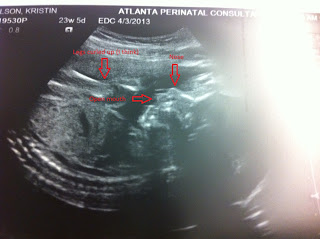

First things first, let me get the 21 week photo out of the way...